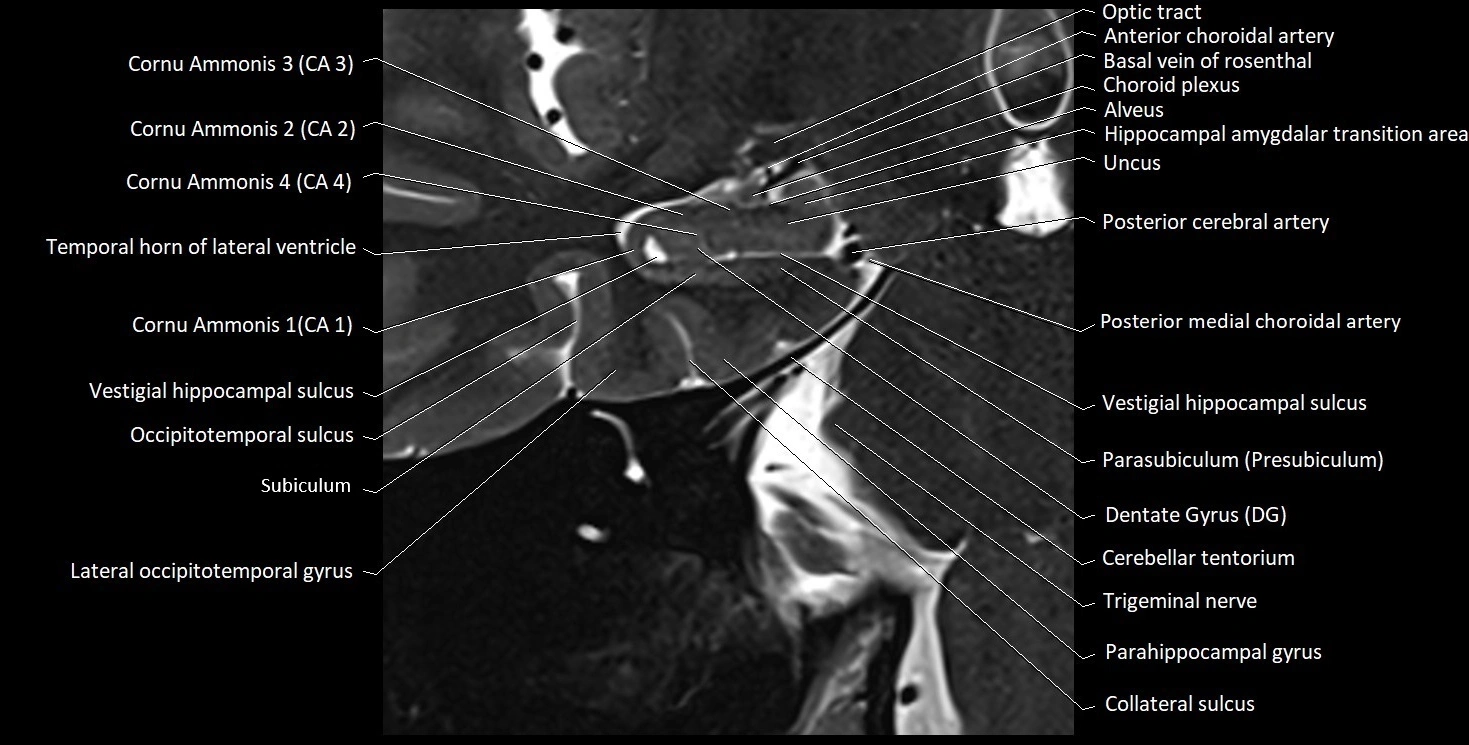

MRI images

image